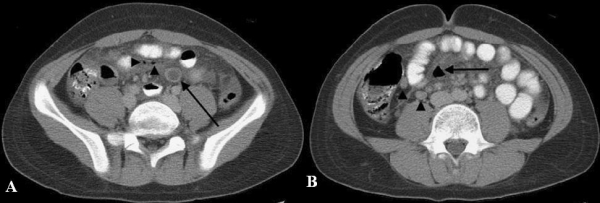

Hình 30: Thủng túi thừa Meckel ở bệnh nhân nữ 22 tuổi bị bệnh Crohn. A, CT thấy ổ abscess ở hố chậu phải (mũi tên),thành hồi tràng đoạn cuối rất dày (dấu sao) thâm nhiễm mỡ mạc treo xung quanh. B, túi thừa Meckel viêm thủng( mũi tên)và dính vào thành bụng trước (dấu sao). (Frank Schwenter, Pascal Gervaz et al (2009). Perforated Meckel’s diverticulitis complicating active Crohn’s ileitis: a case report. Journal of Medical Case Reports, 3:12).